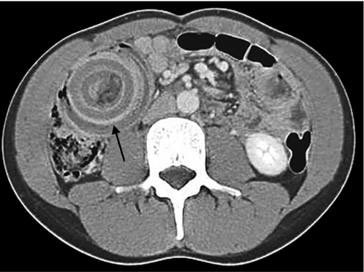

@SIGMOID VOLVULUS - RADIOLOGIC SIGNS OF SIGMOID VOLVULUS 1. COFFEE BEAN SIGN Modality: Plain abdominal X-ray Description: A massively dilated loop of colon with apposed medial walls and a central cleft, resembling a coffee bean. The apex often points toward the right upper quadrant. 2. BIRD Contrast enema (barium or water-soluble) Description: Tapering of contrast at the site of the volvulus, where the twisted colon narrows into a sharp, beak-like appearance. 3. OMEGA LOOP SIGN Modality: Abdominal X-ray Description: A distended loop of sigmoid colon forms an omega (Ω)-shaped shadow. 4. BENT INNER TUBE SIGN Modality: Abdominal X-ray Description: Another term similar to the coffee bean sign; describes the appearance of a closed loop of distended bowel. 5. WHIRLPOOL SIGN Modality: CT scan or sometimes ultrasound Description: Swirling appearance of the twisted mesentery and vessels at the root of the sigmoid mesocolon. 6. INVERTED U SIGN Modality: Abdominal X-ray Description: The dilated sigmoid colon forms an inverted U shape, often centrally or left-sided. 7. FRIMANN-DAHL SIGN Modality: Abdominal X-ray Description: Three dense lines representing the twisted mesenteric folds converging toward the site of torsion. #MedTwitter #MedEd #MedX